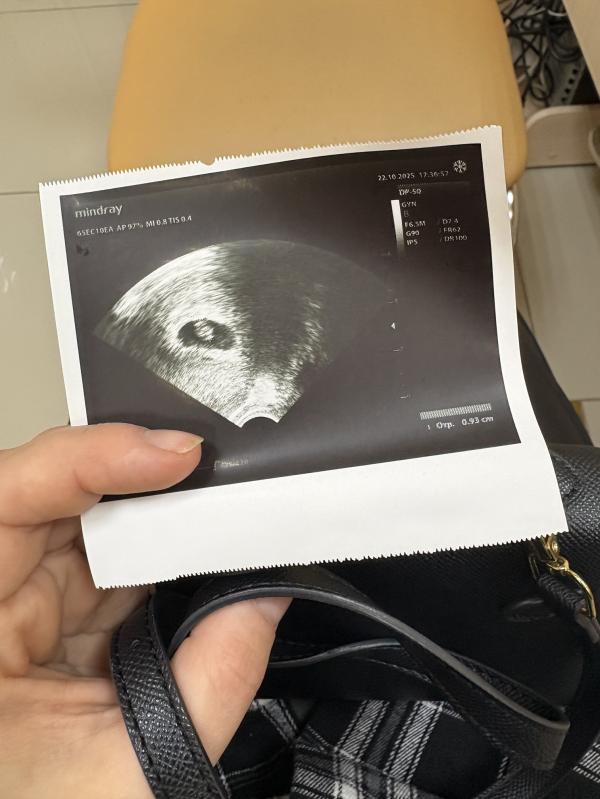

Сходила на первое узи 🤰❤️

Срок 7 недель 🫶🏻

У меня ровно 7 недель

Последние мс 5 сентября